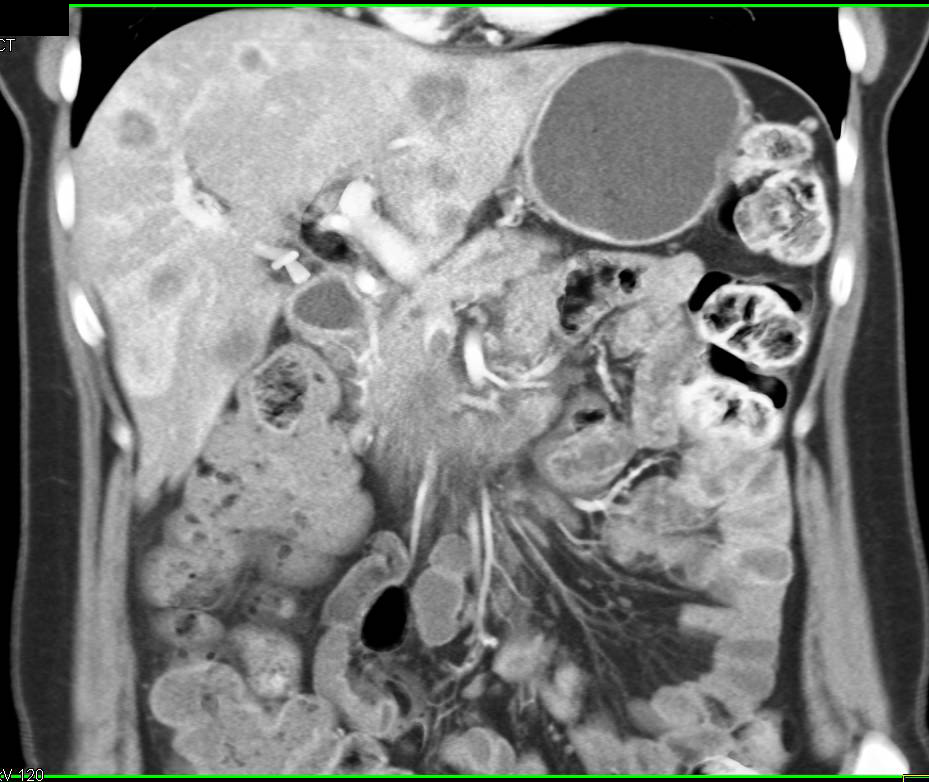

Autoimmune Pancreatitis Simulates a Pancreatic Mass